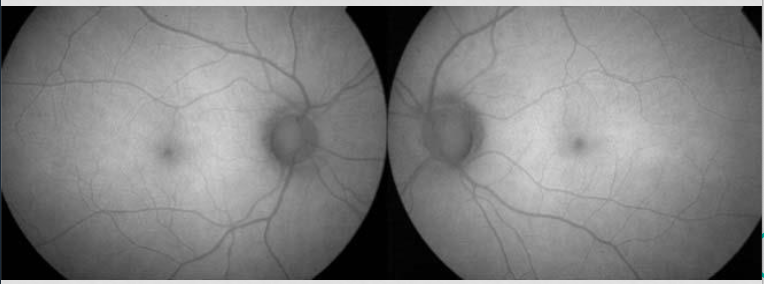

Our pt FAF

hypo macula ; loss of lipofuscin

damaged production of lipofuscin = damaged RPE